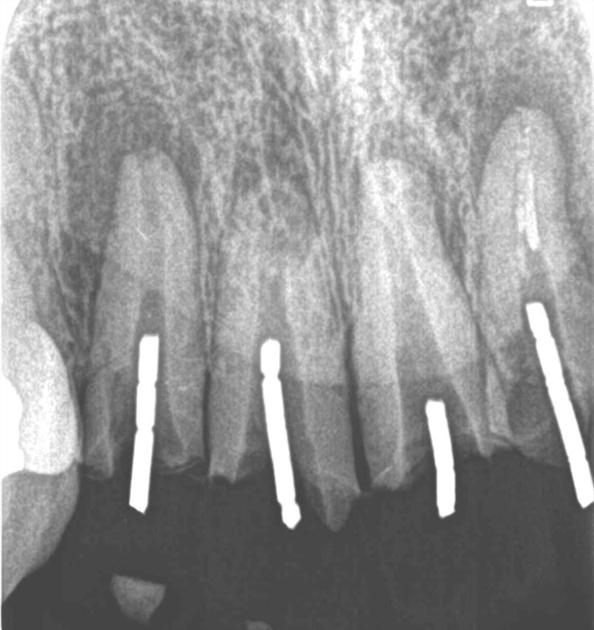

症例5【50代男性】前歯4本の根尖病巣

治療前

治療後(24ヶ月後)